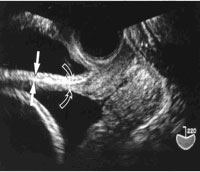

5) TRANS-VAGINAL SONOGRAPHY WITH FULL BLADDER (to the extent that the patient had urge to void):

Measured between 19-39 weeks gestation. The thickness of the urinary bladder was not included in the measurement

Transvaginal sonography showing the lower uterine segment and bladder full. Open arrow indicates uterine wall; solid arrow indicates bladder wall.